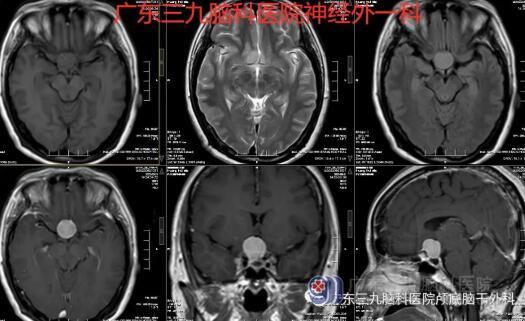

图2:术前MR鞍结节区示范围约20×18×20mm的团块状等T1稍长T2异常信号,FLAIR序列呈不均匀高信号,增强扫描后呈明显强化,邻近脑膜可见强化,邻近视交叉受压;余双侧大脑半球实质内未见异常信号影,灰白质分布均匀,脑室系统未见扩张,脑沟、脑裂及脑池未见增宽,中线结构居中。矢状位示垂体变薄、小脑及脑干未见异常。所见范围内鼻咽部形态、信号未见明显异常。鼻旁窦粘膜增厚。